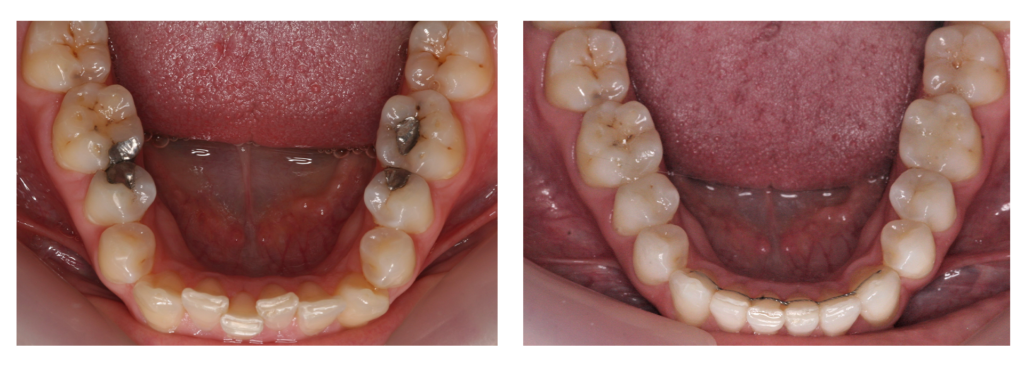

Before & After